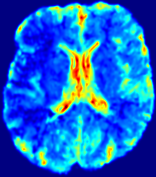

4.3.1 Advection Imaging via Advection-Diffusion

Slice #1Slice #2Slice #3Slice #4Slice #5Slice #6𝐕gt𝟐subscriptnormsuperscript𝐕gt2\|\bf{V}^{\text{gt}}\|_{2}Refer to captionRefer to captionRefer to captionRefer to captionRefer to captionRefer to caption𝐕est𝟐subscriptnormsuperscript𝐕est2\|\bf{V}^{\text{est}}\|_{2}Refer to captionRefer to captionRefer to captionRefer to captionRefer to captionRefer to captionRefer to caption1.51.51.51.21.21.20.90.90.90.60.60.60.30.30.30.00.00.0(mm/s)𝑚𝑚𝑠(mm/s)Destsuperscript𝐷estD^{\text{est}}Refer to captionRefer to captionRefer to captionRefer to captionRefer to captionRefer to captionRefer to caption0.0150.0150.0150.0120.0120.0120.0090.0090.0090.0060.0060.0060.0030.0030.0030.0000.0000.000(mm2/s)𝑚superscript𝑚2𝑠(mm^{2}/s)

Figure 14: PIANO identifiability testing: advection imaging via advection-diffusion. Top row shows 𝐕gt2subscriptnormsuperscript𝐕gt2\|{\bf{V}}^{\text{gt}}\|_{2} used for simulating ground truth pure advection. Rows below show the estimated 𝐕est2subscriptnormsuperscript𝐕est2\|{\bf{V}}^{\text{est}}\|_{2} and Destsuperscript𝐷estD^{\text{est}} on corresponding slices. Note that the plotted value scale for Destsuperscript𝐷estD^{\text{est}} is 0.01 of that for 𝐕gt2subscriptnormsuperscript𝐕gt2\|{\bf{V}}^{\text{gt}}\|_{2} and 𝐕est2subscriptnormsuperscript𝐕est2\|{\bf{V}}^{\text{est}}\|_{2}.

We use the same ‘Advection Imaging’ simulation of Sec. 4.2.1 as the concentration dataset for PIANO. However, instead of modeling pure advection (Eq. 15), we let PIANO estimate both velocity 𝐕estsuperscript𝐕est{\bf{V}}^{\text{est}} and diffusivity Destsuperscript𝐷estD^{\text{est}} via the advection-diffusion PDE (Eq. 2) underlying the proposed PIANO model. Fig. 14 shows the estimated 𝐕est2,subscriptnormsuperscript𝐕est2\|{\bf{V}}^{\text{est}}\|_{2}, and Destsuperscript𝐷estD^{\text{est}} fields for one patient. Although PIANO has the freedom to estimate both a velocity and a diffusivity field from pure advection, PIANO differentiates well between advection and diffusion: the estimated 𝐕est2subscriptnormsuperscript𝐕est2\|{\bf{V}}^{\text{est}}\|_{2} successfully reproduces the ground truth 𝐕gt2subscriptnormsuperscript𝐕gt2\|{\bf{V}}^{\text{gt}}\|_{2} governing the simulated advection process, just as it already did in the ‘Advection Imaging via Advection’ test (Fig. 12). More importantly, the estimated diffusivity Destsuperscript𝐷estD^{\text{est}} is orders of magnitudes smaller than 𝐕est2subscriptnormsuperscript𝐕est2\|{\bf{V}}^{\text{est}}\|_{2}, indicating the estimated diffusion is negligible compared to the estimated advection, which is highly consistent with the underlying pure advection of the simulated data.